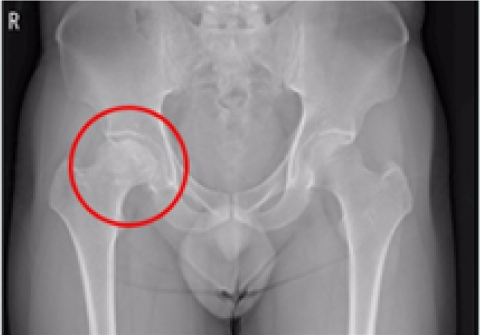

고관절 인공관절 전체치환술

2016.09.26

2017.01.24

고관절 인공관절 부분치환술

2016.10.07

2017.02.09